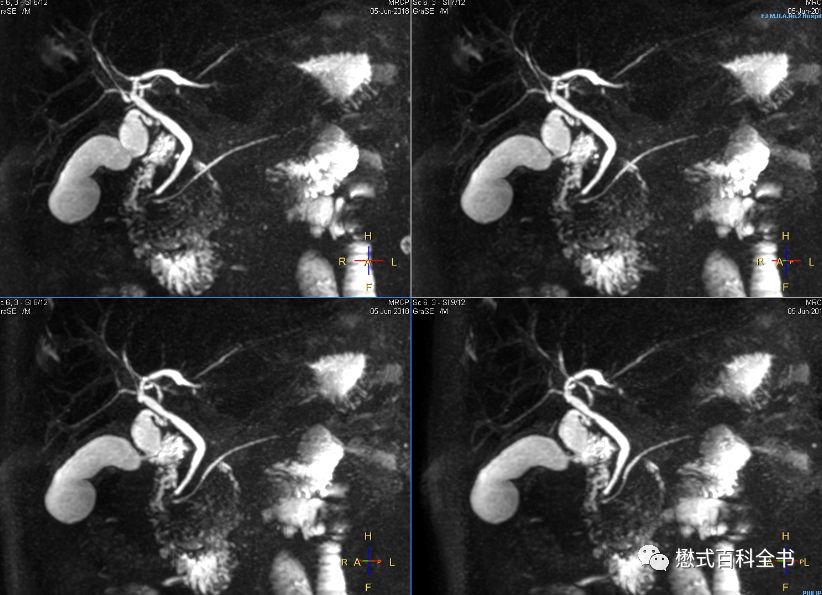

图29、30:常规3D MRCP,扫描时间4:06min

图31、32:使用10倍压缩感知,3D MRCP,扫描时间1:09min

图33、34:使用24倍cs,3D MRCP,扫描时间18s